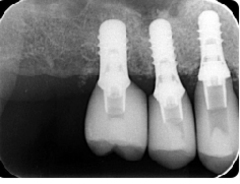

歯周病が進行し、グラグラして物が嚙めず、抜歯してインプラントにしていくことに。

インプラントはストローマンを使用、上部構造はジルコニアセラミックス

費用は2本で総額40万円(税込44万円)(他院の相場だと税込88万円位です)